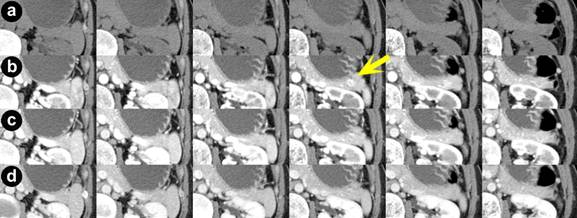

A forty-three-year-old woman was referred due to hypoglycemia. She had repeated episodes consistent with hypoglycemia for one year. Laboratory findings were unremarkable except for a serum glucose of 49 mg/dL. Serum hormone levels were within normal limits. Anti-insulin antibody was negative. Non-invasive imaging modalities including abdominal US, MRI, and routine abdominal CT scan were unremarkable. Angiography showed a tumor stain in the tail of the pancreas. ASVS revealed an elevated insulin level in the hepatic vein but did not effectively localize the lesion. Early-phase thin-slice CT scan (SOMATOM Sensation 64®, Siemens; detector setup 0.75x16 mm, helical pitch 10.5/16 rows, acquired 1.0 mm slices were reformed by 1.0 mm) was performed. Contrast, at a density of 300 mg/mL (Iopamiron 300®, Bayer, Leverkusen Germany) was administered at a dose of 600 mg/kg (for all patients in this report). Timing for the imaging was individualized for each patient. Early phase series at 35 seconds with multiplanar reconstruction after injection of contrast material demonstrated an enhancing 10mm lesion on the dorsal side of the tail of the pancreas, definitively only on one image (Figure 1, yellow arrow). Intraoperative ultrasonography (IOUS) confirmed an 8mm well-demarcated tumor in the tail of the pancreas, and enucleation of the tumor was performed. Pathological findings showed an insulinoma grade G2 with an MIB-1 index <5%. Immunohistochemistry showed chromogranin A (+), synaptophysin (+), insulin (+), EMA (epithelial membrane antigen) (-), and lipase (-). She had an uneventful postoperative course and is without recurrence 39 months postoperatively.

Figure 1. Axial CT scan of Patient #1 (slice thickness: 3 mm) at 0 seconds (pre-contrast) (a.), 35 seconds (b.), 55 seconds (c.), and 80 seconds (d.) after the administration of contrast agent, respectively. Although images of a., c., and d. show no remarkable findings, only one slice in series b. shows a well-enhanced small mass in the tail of the pancreas (indicated by a yellow arrow). |